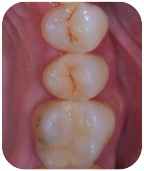

E tu credi che questo dente durerà meno di 3 anni? A meno che non ci sia un cataclisma in questi due mesi, ti posso già anticipare di no, perché a novembre questa cura compirà tre annetti e il dente è perfetto sia clinicamente che radiograficamente.

Riassorbimento esterno - Finale BongioanniRiassorbimento esterno - Radiografia finale Bongioanni